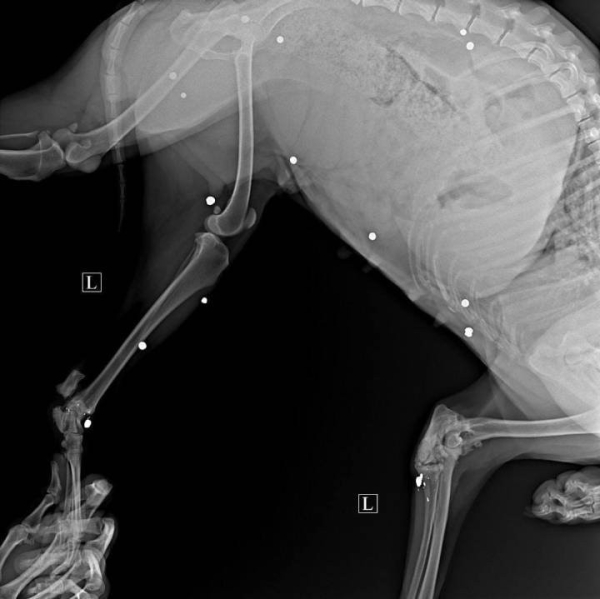

В начале февраля гродненские волонтеры нашли в городском поселке Сопоцкин хромую собаку. При первичном осмотре врача в Гродно появились предположения, что в теле животного есть пули. Рентгеновский снимок это подтвердил – собака в прямом смысле «нафарширована» пулями.

В теле у дворняги около 20 пуль. Сейчас милиция и волонтеры ищут хоть какие-то зацепки, кто совершил этот зверский поступок. Почитайте материал, может, вы им поможете.

При первичном осмотре у врача появились предположения, что в теле у собаки есть пули – они прощупывались под кожей. Рентгеновские снимки это подтвердили – в теле у дворняги насчитали около 20 пуль. Уже потом при кастрации удалось одну пулю достать, рассказывает волонтер.

— В заключении врач пишет, что у собаки застарелые переломы с признаками частичного заживления. В различных частях тела обнаружены инородные предметы размером около 4-5 мм, похожее на снаряд для пневматического оружия. Судя по всему, раны не свежие. А по локализации пуль, можно сделать вывод, что в собаку стреляли прицельно с целью убить или поиздеваться. Вероятнее всего, она находилась либо в помещении, либо привязана.